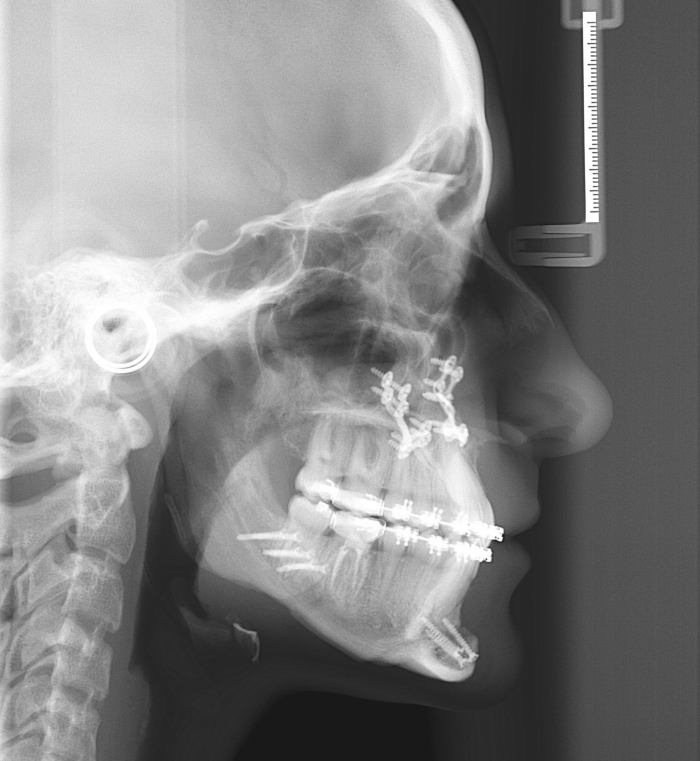

Telerradiografia perfil após a cirurgia  - Clínica Cliniface

Telerradiografia perfil após a cirurgia